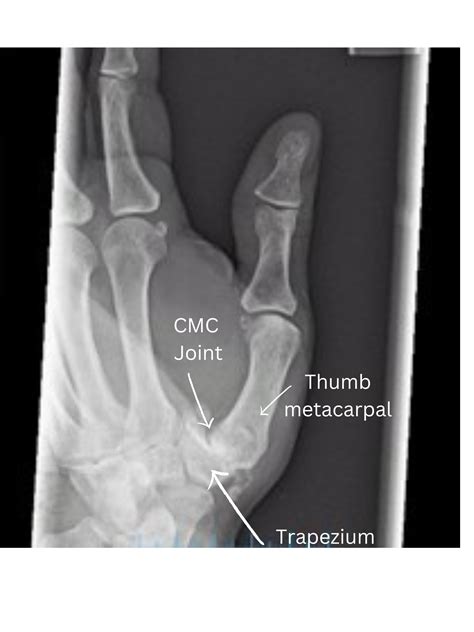

• Carpometacarpal (CMC) Joint: This is the joint at the base of the thumb where it connects to the wrist.

• Imaging Tests: X-rays, MRI, or ultrasound to visualize the joint and surrounding tissues.

• joints in the thumb diagram

• thumb joints anatomy

• cmc joint thumb